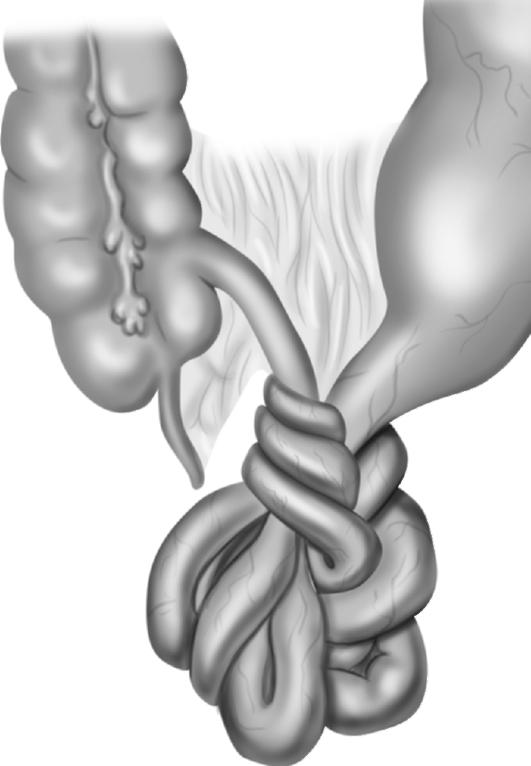

Иллюстрации и информация о симптомах острого кишечного непроходимости